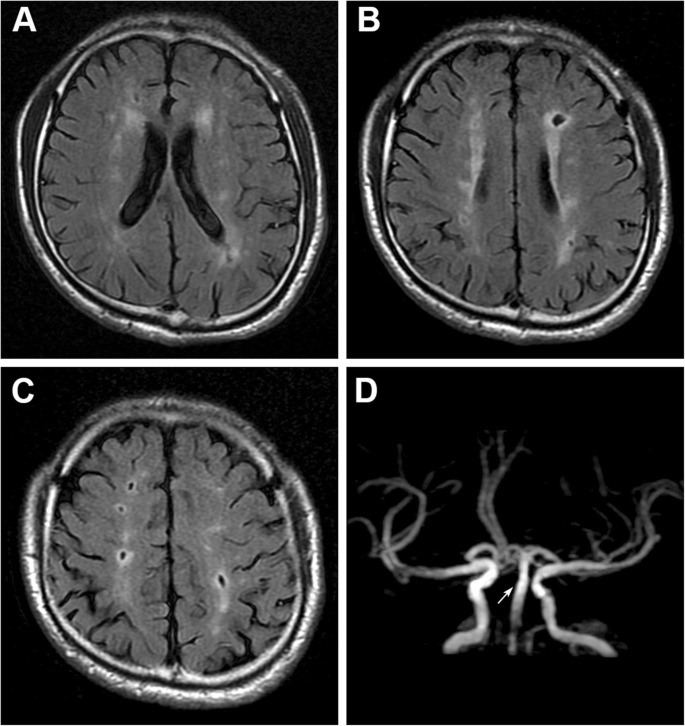

四、脑白质脱髓鞘。

面对一份头部的CT报告单,最常见的字眼其实就是脑白质脱髓鞘了,对于这种问题该怎么解决呢?

其实对于大多数患者,并不需要解决。

看上去脑白,质脱髓鞘是一种疾病,可是实际上只要岁数到了,或多或少都会有这种情况,轻度的脑白质脱髓鞘在55岁以上的人群当中其实是很常见的。

当然,很多人虽然有脑白质脱髓鞘,但并没有什么症状也没有什么感觉。

对于这类患者其实并不需要治疗,症状较轻的时候也没有什么好的治疗方式可以改善,最重要的就是强调改善生活方式,把自己大脑子的状态调整好。

但是要小心,如果是非常严重的脑白质脱髓鞘可能就是一种疾病了,我们也应该好好的治疗,比如脑神经炎,而且出现头痛。